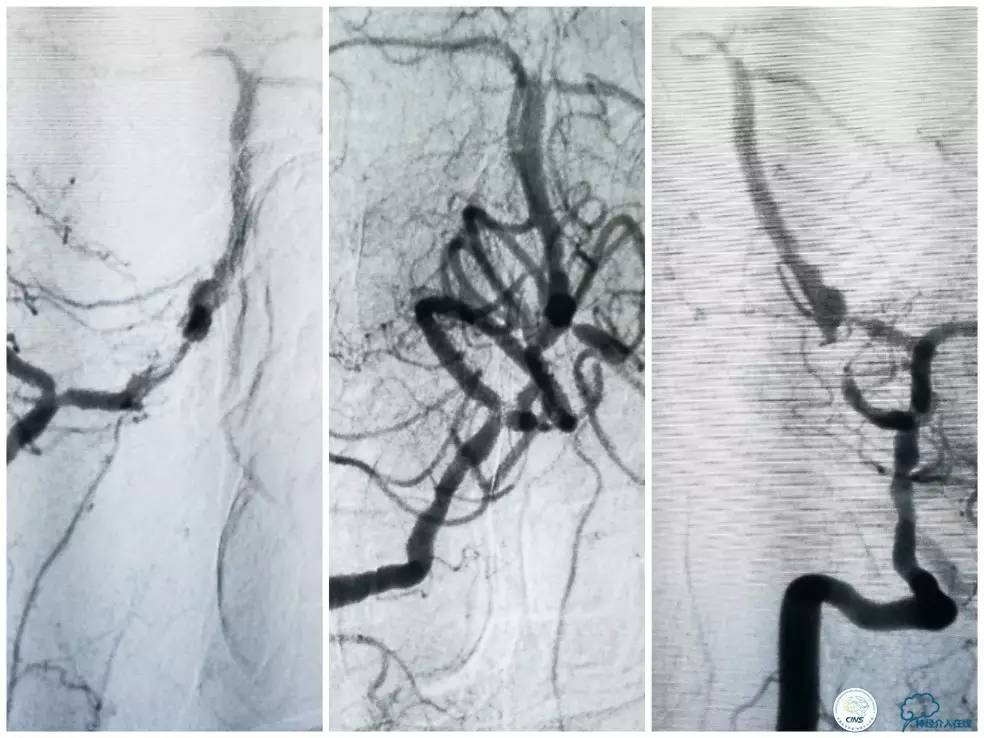

遂再次将Transend微导丝送至右大脑后动脉P1段,使用Gateway球囊(2.0mm×15mm)于支架最狭窄处后扩张(图15)。

图15

其后造影显示支架贴壁良好,远端血管显影好,前向血流TICI3级(图16)。

图16